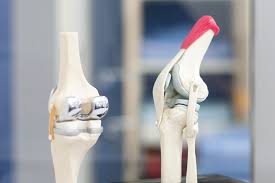

무릎 인공관절 수술, 왜 필요한가요?

무릎관절은 체중을 가장 많이 지탱하는 관절입니다. 나이가 들수록 연골은 점차 마모되고, 충격을 흡수하는 능력도 감소합니다. 이로 인해 통증, 뻣뻣함, 운동 제한이 생기며, 이런 증상이 악화되면 인공관절 수술이 필요해집니다.

퇴행성 관절염 외에도 류마티스 관절염이나 외상 후 관절 손상이 심각할 경우 수술이 권유되며, 수술을 통해 환자는 통증 없이 보행이 가능해지고 일상생활로 복귀할 수 있게 됩니다.